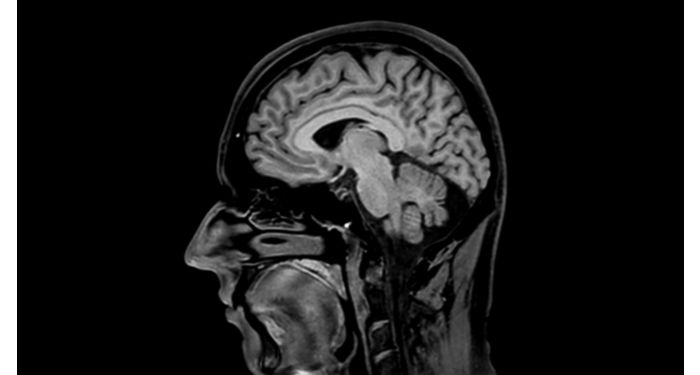

70 % der Radiologen betrachten neurologische Indikationen als schwierig, meist wegen des Mangels an geeigneten Bildgebungs- und Visualisierungsverfahren¹. Deshalb ist es das erklärte Ziel von Philips, bestmögliche diagnostische Klarheit und Unterstützung für die Behandlung aller Patienten mit neurologischen Störungen zu liefern. Mit Hilfe unserer digitalen Plattform dStream führen wir dieses Jahr eine Reihe neuartiger Bildgebungs- und Visualisierungsstrategien ein. Dies verschafft Ihnen größere Sicherheit bei der Beantwortung komplexer neurologischer Fragestellungen und ermöglicht Ihnen die Erschließung neuer neurologischer Bereiche in erweiterten neurofunktionalen Anwendungen. Es handelt sich dabei um einen entscheidenden Schritt in Richtung einer Aufwertung der neurologischen Diagnostik und führt letztendlich dazu, dass mehr Patienten von der Magnetresonanztomographie profitieren. ¹ TMTG-Marktstudie 2016

Klinische Fallbeispiele für nahezu jede anatomische Struktur Sehen Sie sich mehr als 100 klinische Fallbeispiele von Kollegen auf der ganzen Welt an, die zeigen, wie die digitale MR-Technologie von Philips Ihre Anforderungen in der Bildverarbeitung unterstützt.